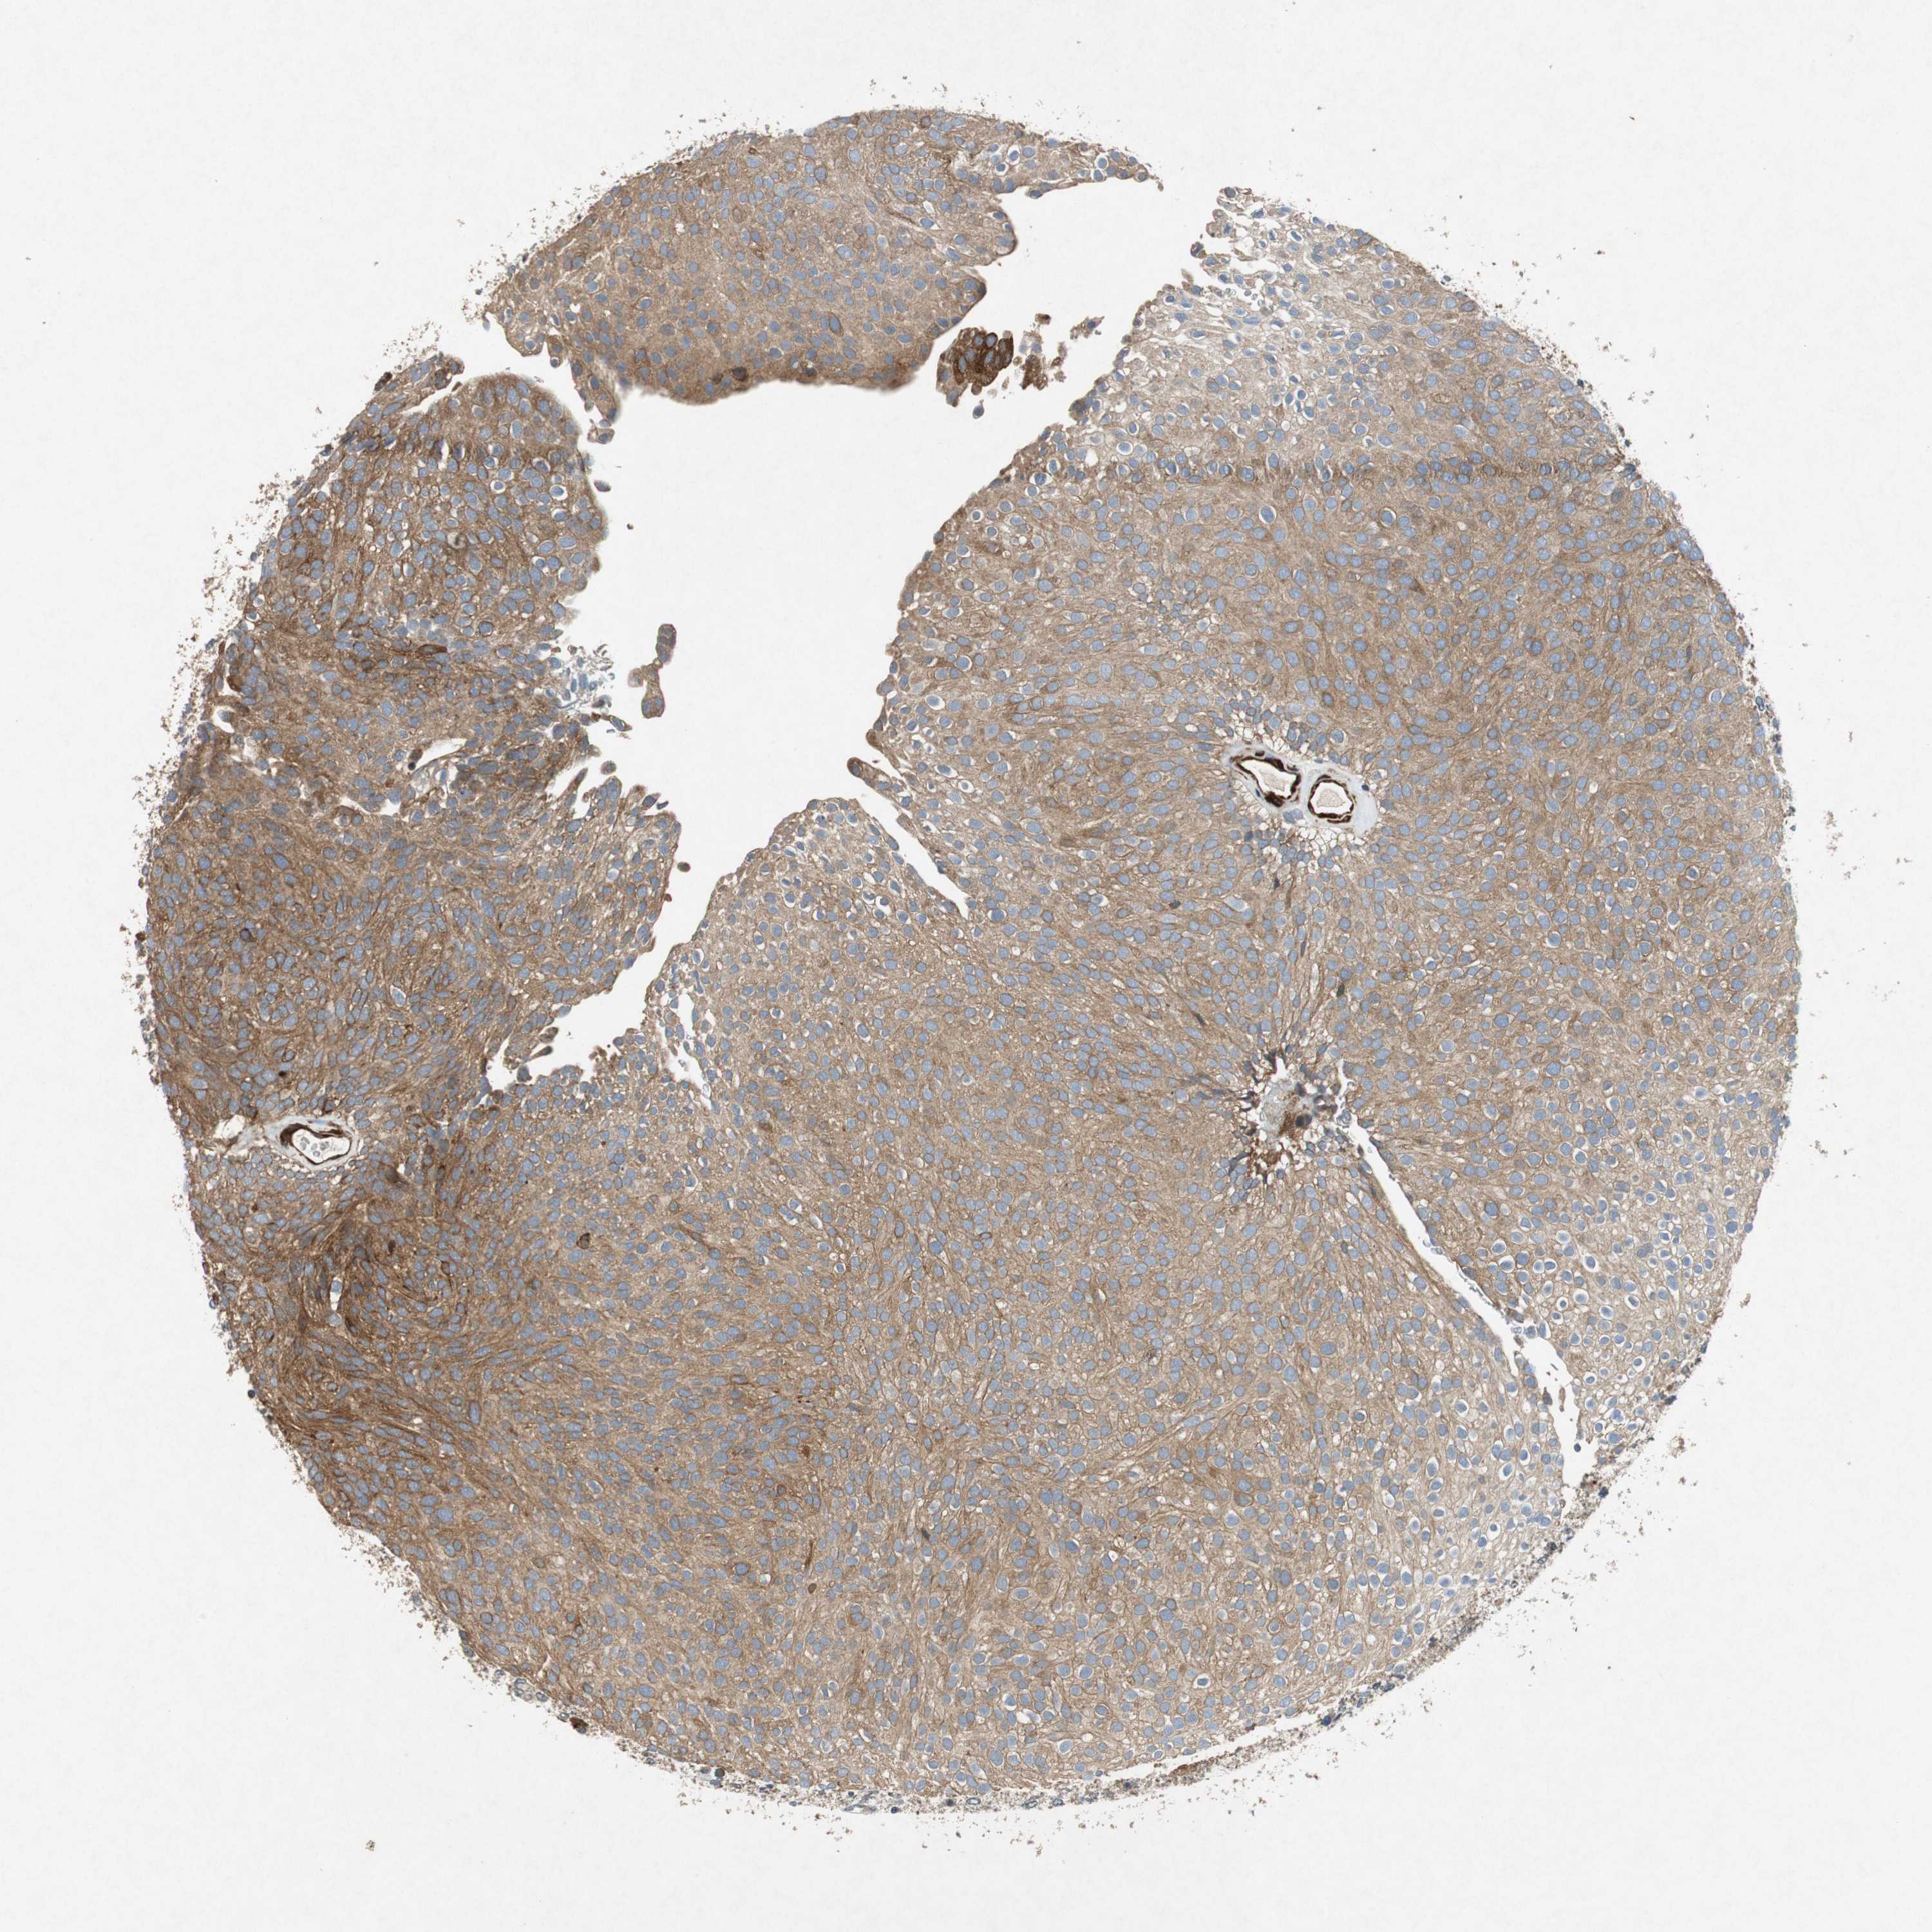

UROTHELIAL CANCER - Protein expressioni

A mouse-over function shows sample information and annotation data. Click on an image to view it in a full screen mode. Samples can be filtered based on level of antibody staining by selecting one or several of the following categories: high, medium, low and not detected. The assay and annotation is described here.

Note that samples used for immunohistochemistry by the Human Protein Atlas do not correspond to samples in the TCGA dataset.

Antibody stainingi

Antibody staining in the annotated cell types in the current human tissue is reported as not detected, low, medium, or high, based on conventional immunohistochemistry profiling in selected tissues. This score is based on the combination of the staining intensity and fraction of stained cells.

Each image is clickable and will lead to virtual microscopy that enables deeper exploration of all samples and also displays staining intensity scores, fraction scores and subcellular localization as well as patient and tissue information for each sample.

HPA039247

HPA043684

HPA063394

CAB004621

CAB005887

Staining

High

Medium

Low

Not detected

Intensity

Strong

Moderate

Weak

Negative

Quantity

>75%

75%-25%

<25%

None

Location

Nuclear

Cytoplasmic/membranous

Cytoplasmic/membranous,nuclear

Urothelial carcinoma, High grade

Urothelial carcinoma, Low grade